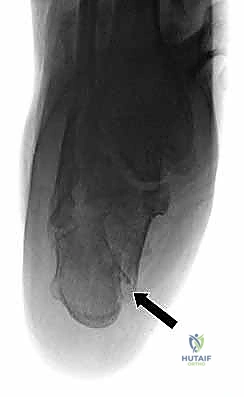

- التصوير بالأشعة السينية (X-rays): لأخذ فكرة أولية عن الكسر (زوايا بوهلر وجيسان - Bohler’s and Gissane’s angles).

- الأشعة المقطعية (CT Scan): وهي الخطوة الأهم والأكثر حيوية. توفر الأشعة المقطعية صوراً ثلاثية الأبعاد وتقاطعاً دقيقاً للكسر، مما يسمح بتصنيف الكسر (نظام ساندرز - Sanders Classification) وتحديد عدد الشظايا العظمية ومدى انزياحها داخل المفصل. بناءً على هذه الأشعة، يضع الدكتور هطيف خطته الجراحية الدقيقة.